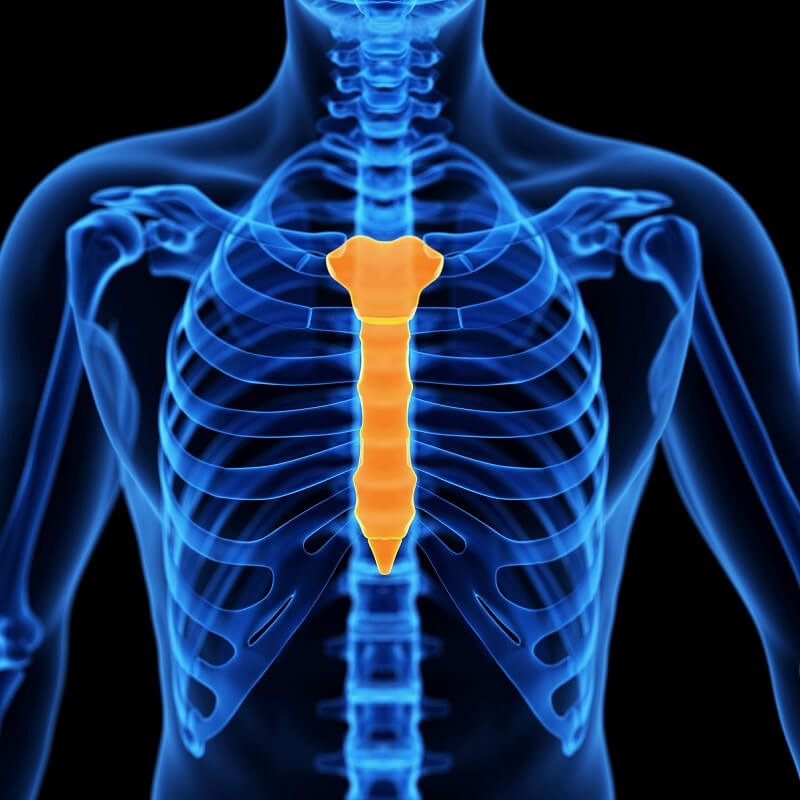

1- El esternón

El esternón tiene forma de corbata y se encuentra en el centro del pecho. Los siete primeros pares de costillas están conectados directamente al esternón; los pares 8, 9 y 10 están unidos al esternón a través de cartílagos.

Los dos pares inferiores, a diferencia del resto, no están conectados de ningún modo al esternón, por lo que son llamadas “costillas flotantes”. En el esternón, se distinguen tres partes:

- Parte superior, que es denominada manubrio o mango.

- Parte media, llamada cuerpo del esternón.

- Parte inferior, denominada punta o apéndice xifoides.